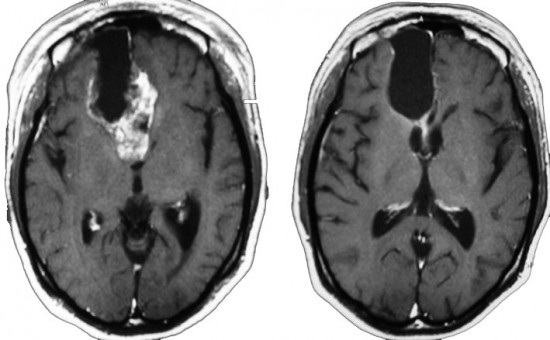

若い成人です,認知機能障害で発症しました。この画像を見るからに悪性神経膠腫,少なくともグレード3のグリオーマであることは明白です。しかし,グレード4膠芽腫あるいはグレード3退形成性星細胞腫にしては腫瘍周辺浮腫が軽すぎます。ですから,グレード3の退形成性乏突起膠腫 AO かも。認知機能の回復と温存を考量して,脳梁損傷と前交連損傷を避けて,右上前頭回と帯状回腫瘍を摘出しました。

左は術後のT1強調ガドリニウム増強像で,残存腫瘍がわかります。この腫瘍に対してICE (IFO/CDDP/VP-16) 化学療法を1コースしました。右側のMRIが1ヶ月後の画像です。このように1p/19q欠失のある退形成性乏突起膠腫は,化学療法感受性がとても高い悪性グリオーマです。ですから,手術で後遺症を残さないように,勢い込んで腫瘍を摘出しようとしないことが大切です。光顕診断はAOで,後々の解析で1p/19q codeletion でした。